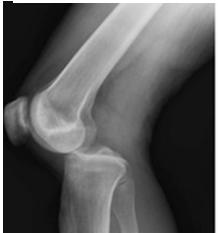

Типи з’єднання кісток. Кістки можуть бути з’єднані одна з одною в різний спосіб. Виділяють три типи таких з’єднань: 1) нерухомі коли зміщення між кістками майже не можливі (зокрема шви з’єднання кісток склепіння черепа в дорослих); 2) напіврухомі з’єднання з допомогою хрящового прошарку, за рахунок пружності якого можливі обмежені рухи (міжхребцеві з’єднання); 3) рухомі, або суглобові з’єднання, що забезпечують найбільші за амплітудою рухи. Суглоб (іл. 61) має такі складники: 1) суглобові поверхні двох або більше кісток, укриті хрящем; 2) суглобова сумка (або капсула), що відмежовує суглоб від навколишніх тканин і формує порожнину; 3) суглобова рідина, що заповнює порожнину суглобової сумки, зменшує тертя під час рухів, живить хрящ і забезпечує амортизацію суглоба. За формою виділяють кулясті суглоби (плечовий), циліндричні

Іл. 61. Будова колінного